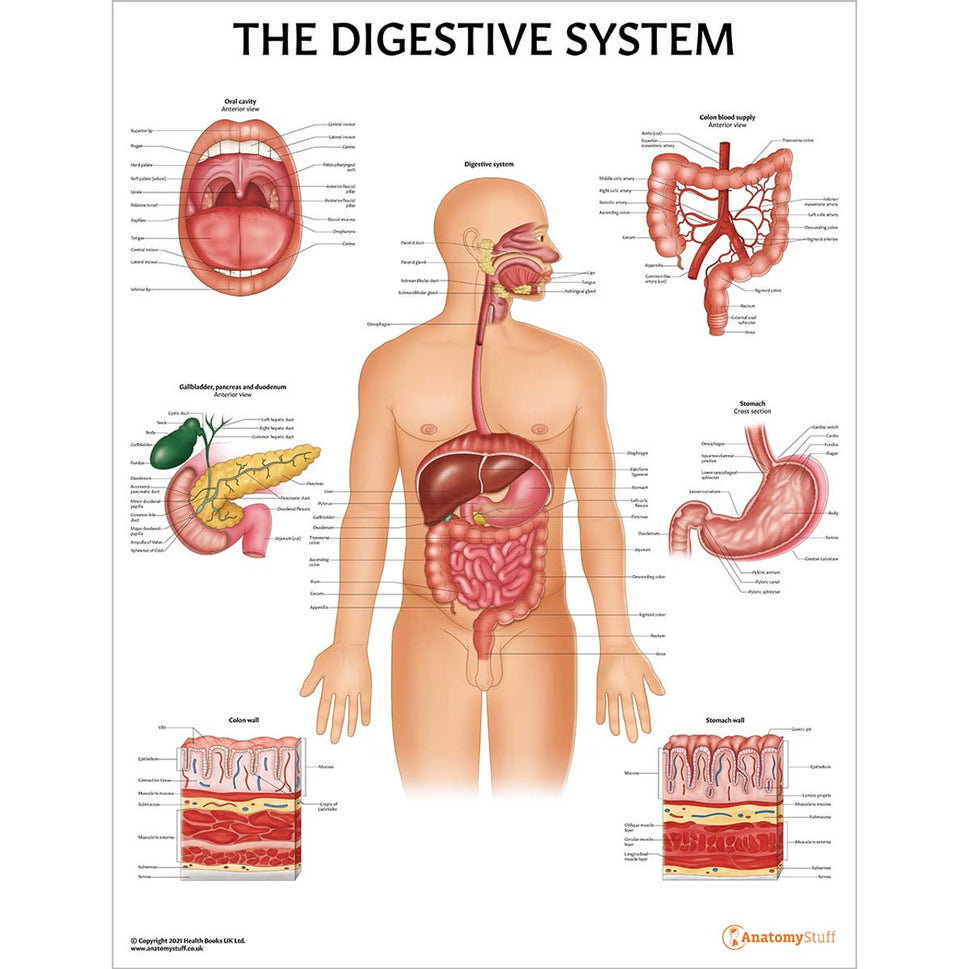

Enhance medical education with our collection of digestive system anatomical models including the stomach, liver, gallbladder, pancreas & colon models. Discover the anatomy of healthy organs as well as common gastrointestinal diseases such as stomach ulcers, gallstones and liver cirrhosis. Our digestive system anatomy posters are ideal for study and patient education.

At AnatomyStuff we stock a diverse range of digestive system anatomical models to suit your training needs. From budget models and affordable medical education posters to highly advanced 3D printed bowel models, you can transform medical training and patient education. As well as our own exclusive collection, we are proud resellers of 3B Scientific, Anatomy Lab, Denoyer-Geppert Science Company, ESP Models, Erler Zimmer and GPI Anatomicals. Explore our exclusive collection of digestive system anatomy charts, posters, fine art prints and digital anatomy study guides. Discover the anatomy of key organs like the liver, stomach, pancreas and bowel as well as the pathophysiology of common conditions like peptic ulcer disease, coeliac disease, IBD and much more. We have anatomy posters suitable for school children all the way up to medical degree level. From a liver anatomy poster to a digital study guide all about common GI disorders, find exactly what you need right here to enhance medical training and patient education.